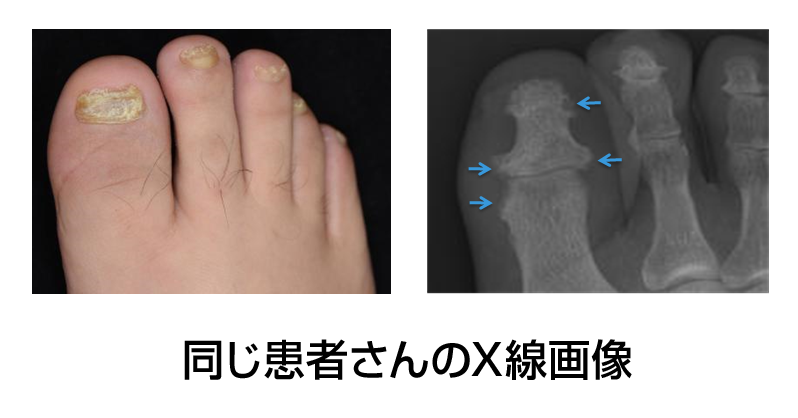

(図2)爪症状と関節症性乾癬による骨破壊

臨床検査値などで明確に予測できるものは確立されていないのですが、実際に関節症性乾癬になった方の傾向を調べると「爪、頭、おしり(肛門周囲)」のいずれかに乾癬の症状があった方が多かったという報告があります。したがって頭部の症状でフケがたくさん出る方や肛門の上のところの皮膚が切れたりカサカサしている方は要注意です。爪症状はそれだけでQOLを大きく障害する症状ですが、関節症性乾癬の相関を示す報告も多く注目されています。爪乾癬がある足の指が時々痛む、という方のレントゲン写真をとったところ、すでに指の骨破壊が進んでいたという例もありました。(図2)